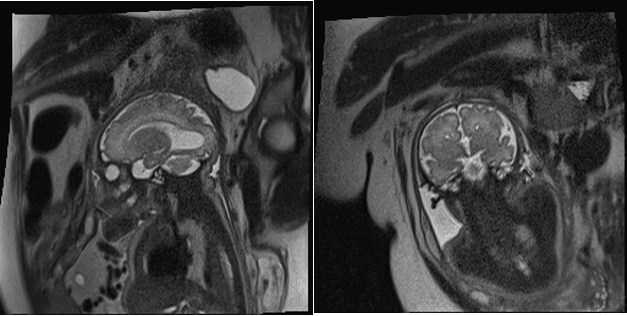

Fetal MRI was performed in three cases. It confirmed the ultrasound suspicion of ACC and revealed no additional anomalies. The remaining two corresponded to ventriculomegaly—one severe and one associated with dilation of the suprapineal recess—suggesting a possible but unconfirmed obstructive etiology (Figures 1-3).

Figure 1. Colpocephalic dilatation of the left ventricle.

<b>Figure 1.</b> Colpocephalic dilatation of the left ventricle.